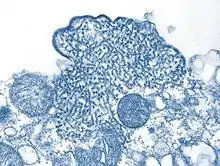

| Structure of a Henipavirus | |